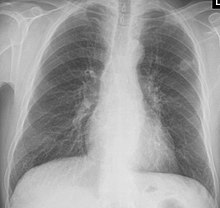

Je weicher die Strahlung (niedrige kV-Werte) ist, desto größer ist der Anteil der vom Gewebe absorbierten Strahlung. Dadurch werden auch feinste Gewebeunterschiede auf dem Röntgenfilm sichtbar gemacht. Dies ist der Fall bei der Mammografie (Röntgenuntersuchung der weiblichen Brust), jedoch ist die Strahlenbelastung des durchstrahlten Gewebes dadurch relativ hoch. Harte Strahlung (über 100 kV) durchdringt Gewebe und Materialien (Gips und sogar Bleischürzen von geringerer Dicke) wesentlich leichter. Kontrastunterschiede werden stark abgemildert, wie z. B. bei Lungenaufnahmen (120 kV), bei denen sonst im Bereich der Rippen keine Beurteilung der Lungenstruktur möglich wäre.

Beispiel: Bei der Koronaruntersuchung mittels Computertomographie (CT) erkaufen sich Patienten die erhöhte Sensitivität mit einem gesteigerten Krebsrisiko. So errechneten amerikanische Wissenschaftler, dass bei Zwanzigjährigen eine von 143 mittels Koronar-CT untersuchten Frauen im Laufe ihres Lebens infolge dieser Angiographie-Strahlung an Krebs erkrankt, aber nur einer von 686 gleich alten Männern. Die CT-Angiographie der Koronarien scheint vor allem bei Frauen und jungen Menschen das Krebsrisiko nicht unerheblich zu erhöhen.[13] Kommt ein Patient mit akutem Myokardinfarkt in die Klinik, wird ihm oft eine Strahlendosis von insgesamt 14,5 mSv verabreicht, was etwa 73 Thorax-Röntgen-Bildern entspricht. Die Dosis, die ein Infarktpatient durch diese Katheteruntersuchung erhält, entspricht 3/4 der gesetzlich festgelegten Jahresdosis für Arbeiter in deutschen Kernkraftwerken (20 mSv/a).[14]

In einer groß angelegten Studie hatten sie die Daten von 64.074 Patienten analysiert, die zwischen 2006 und 2009 in Lehrkrankenhäusern der USA wegen eines akuten Herzinfarktes behandelt worden waren. Insgesamt wurden in diesem Zeitraum 276.651 Untersuchungen mit ionisierenden Strahlen an diesem Kollektiv durchgeführt. 83 % der Herzinfarktpatienten erhielten Röntgenaufnahmen des Thorax, 77 % Katheteruntersuchungen. Zwar sollten laut Meinung des Referenten notwendige Untersuchungen, die ionisierende Strahlen beinhalten, nicht unterbleiben – man sollte aber sicher sein, dass diese angemessen sind.